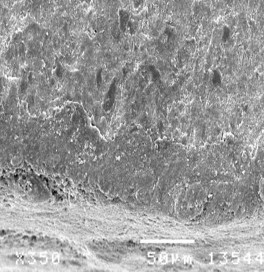

Hình 3.18: Hình ảnh sâu răng D1 sau điều trị bằng ClinproTM XT varnish ở độ phóng đại 500 lần.

Hình 3.19: Hình ảnh trụ men sau điều trị bằng ClinproTM XT varnish ở độ phóng đại 750 lần.

Hình 3.20: Hình ảnh sâu răng D1 sau điều trị bằng ClinproTM XT varnish ở độ phóng đại 1000 lần.